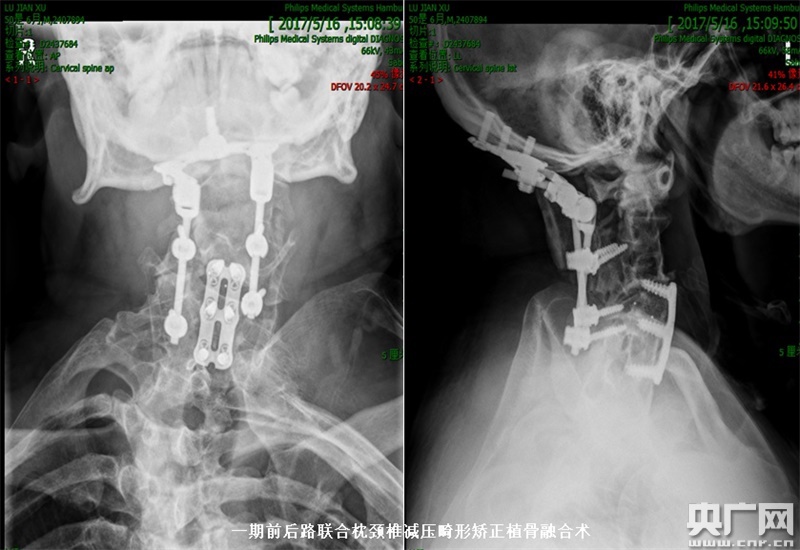

術(shù)后頸椎正側(cè)位X片:一期前后路聯(lián)合枕頸椎減壓畸形矯正植骨融合術(shù)。